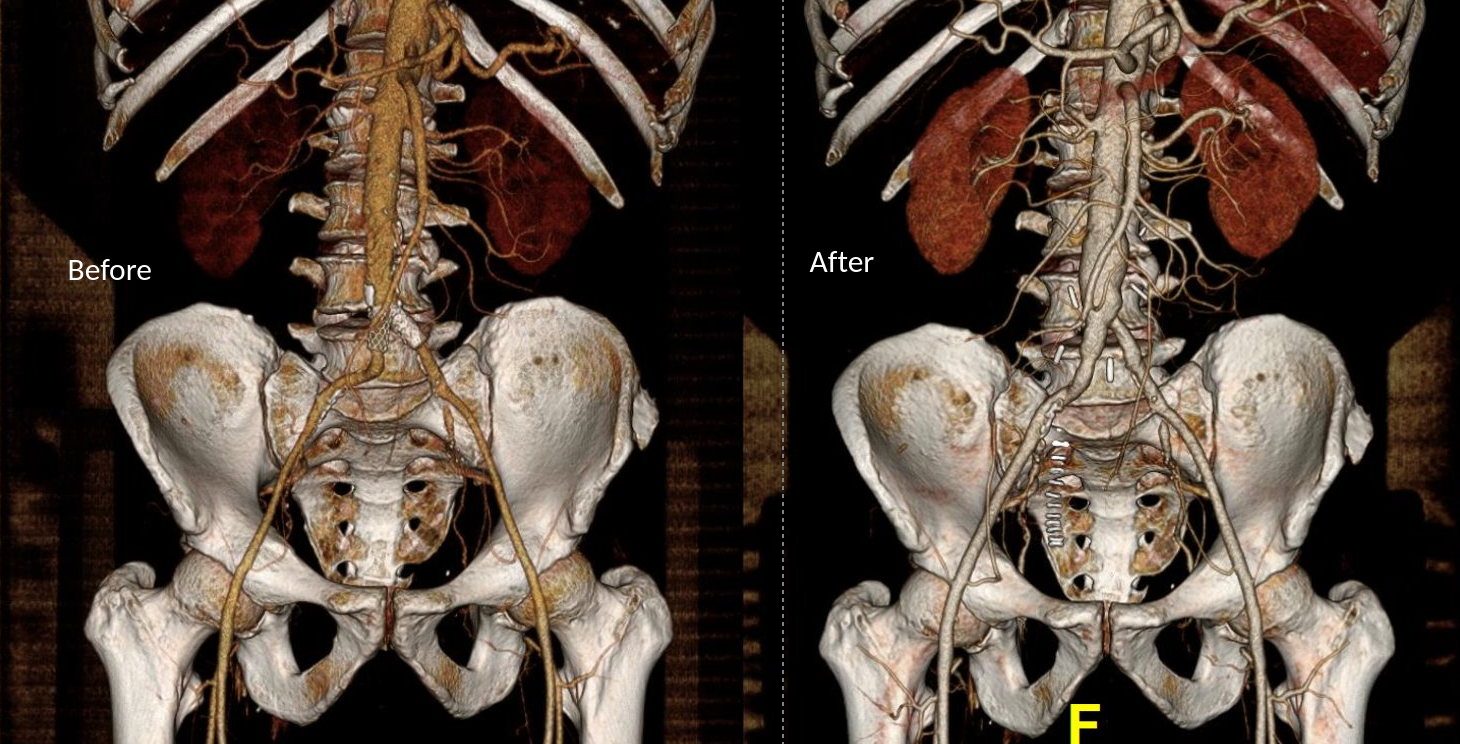

The image above shows a common femoral artery aneurysm presenting as a pulsatile mass in the right groin. The first image on left is an arteriogram (a sketch of one) that I would get prior to surgery. The patient is also suffering from pain in the right leg due to a lack of blood flow because his superficial femoral artery (SFA) is occluded and his profunda femoral artery (PFA) is open but has a blockage at its origin where the aneurysm ends. I plan the surgery and execute it. During surgery, things may pop up -good things like finding an otherwise pristine SFA filled with plaque. Removing the plaque, it becomes a great conduit for replacing the aneurysm and avoids using an expensive graft which can become infected -your own tissues fight off infection better than graft.